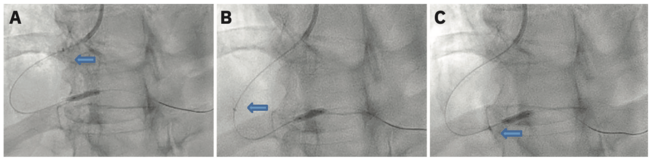

There are three different techniques that we use to deliver the guide catheter extension system. One is called the balloon surfing technique. The balloon surfing technique or balloon assisted tracking starts by deploying either a 2 or a 2.5 mm balloon at the tip of the catheter, with half sticking out of the catheter. The balloon is actually used as a bumper in an attempt to get past the lesion or to the lesion. A second technique called the balloon tracking technique or balloon anchor (Figure 1) is the most common technique I use. It entails inflating the balloon, whether a compliant or noncompliant balloon, at the distal vessel where the lesion is located, and while the balloon is up, tracking the guide catheter extension system to the lesion, to the balloon. It is almost like a balloon anchor. Whenever you are delivering the guide extension catheter system, it should always be done over a present balloon shaft or stent shaft. The reason is based on the old teaching that we should never go “bare,” meaning you should not push the guide extension catheter over a wire without any assisting balloon, because it can cause trauma to the vessel. The biggest complication that we see with guide extension catheters is dissection. Both the balloon surfing and the balloon tracking techniques allow for the presence of a stiffer shaft or a stiffer rail system for the guide extension catheter system to go over, thus limiting or preventing trauma to the vessel wall, and so these are the two main techniques we use to deliver the guide extension catheter system. Once the guide extension catheter system is at the balloon, there is also a technique called “inchworming” (Figure 2). After the balloon is inflated and as it is deflating, we push the guide extension catheter over the balloon. We will use the inchworming technique if there is significant proximal stenosis and we can’t get the guide extension past that stenosis to get to the lesion. We often will inflate a balloon at that proximal lesion, and as the balloon is coming down, push the guide extension catheter over the balloon, past the stenosis. A stent or an IVL balloon can then be delivered by unsheathing the guide extension catheter, because you are past the lesion. The use of these three techniques is crucial for IVL delivery in the treatment of calcified lesions. Without these techniques, delivering these devices becomes very difficult. Another problem is that when you are going through calcified and tortuous lesions, the balloon, the IVL catheter, and the stent can become damaged. The guide extension catheter actually protects devices from getting damaged. The biggest risk for IVL catheters is obviously balloon damage leading to a balloon rupture, which could then lead to dissection or damage to the arteries. Stents themselves can either be damaged and/or their drug coating can be damaged. Even worse is that the stent could be stripped off the balloon and you now have a freestanding stent in a vessel with calcified lesions. Guide extension catheter systems can prevent these complications from happening and it is absolutely crucial that interventionalists know how to use guide extension catheters.